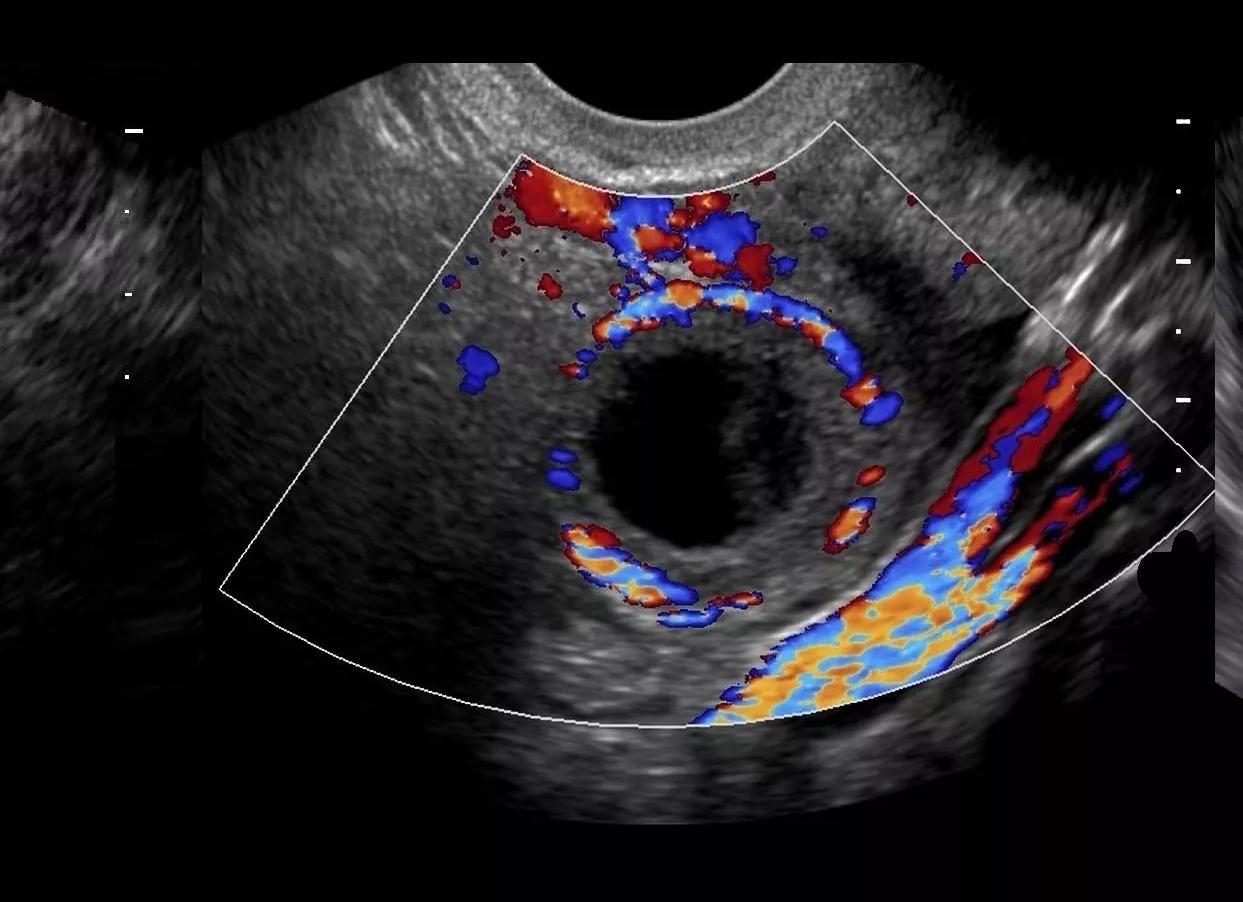

Как выглядит желтое тело на УЗИ?

В подавляющем большинстве случаев само желтое тело яичника не является основной целью поиска на УЗИ. Чаще всего оно бывает случайной находкой, а в случае диагностики нарушений цикла или бесплодия — показателем свершившейся овуляции. Желтое тело на УЗИ дает достаточно интересную и многообразную картину:

- Неправильной формы, с толстым краем и даже валиком.

- С неровным «фестончатым» краем.

- Находится в яичнике на месте бывшего фолликула. Иногда частично представляет собой сгусток крови, образовавшийся после разрыва фолликула.

- Внутренняя его структура на УЗИ крайне разнообразна, может включать кистозные полости и даже кровоизлияния.

- Кровоток при ЦДК по периферии очень активный. Это неудивительно, ведь временный орган должен хорошо кровоснабжаться для нормальной его работы.